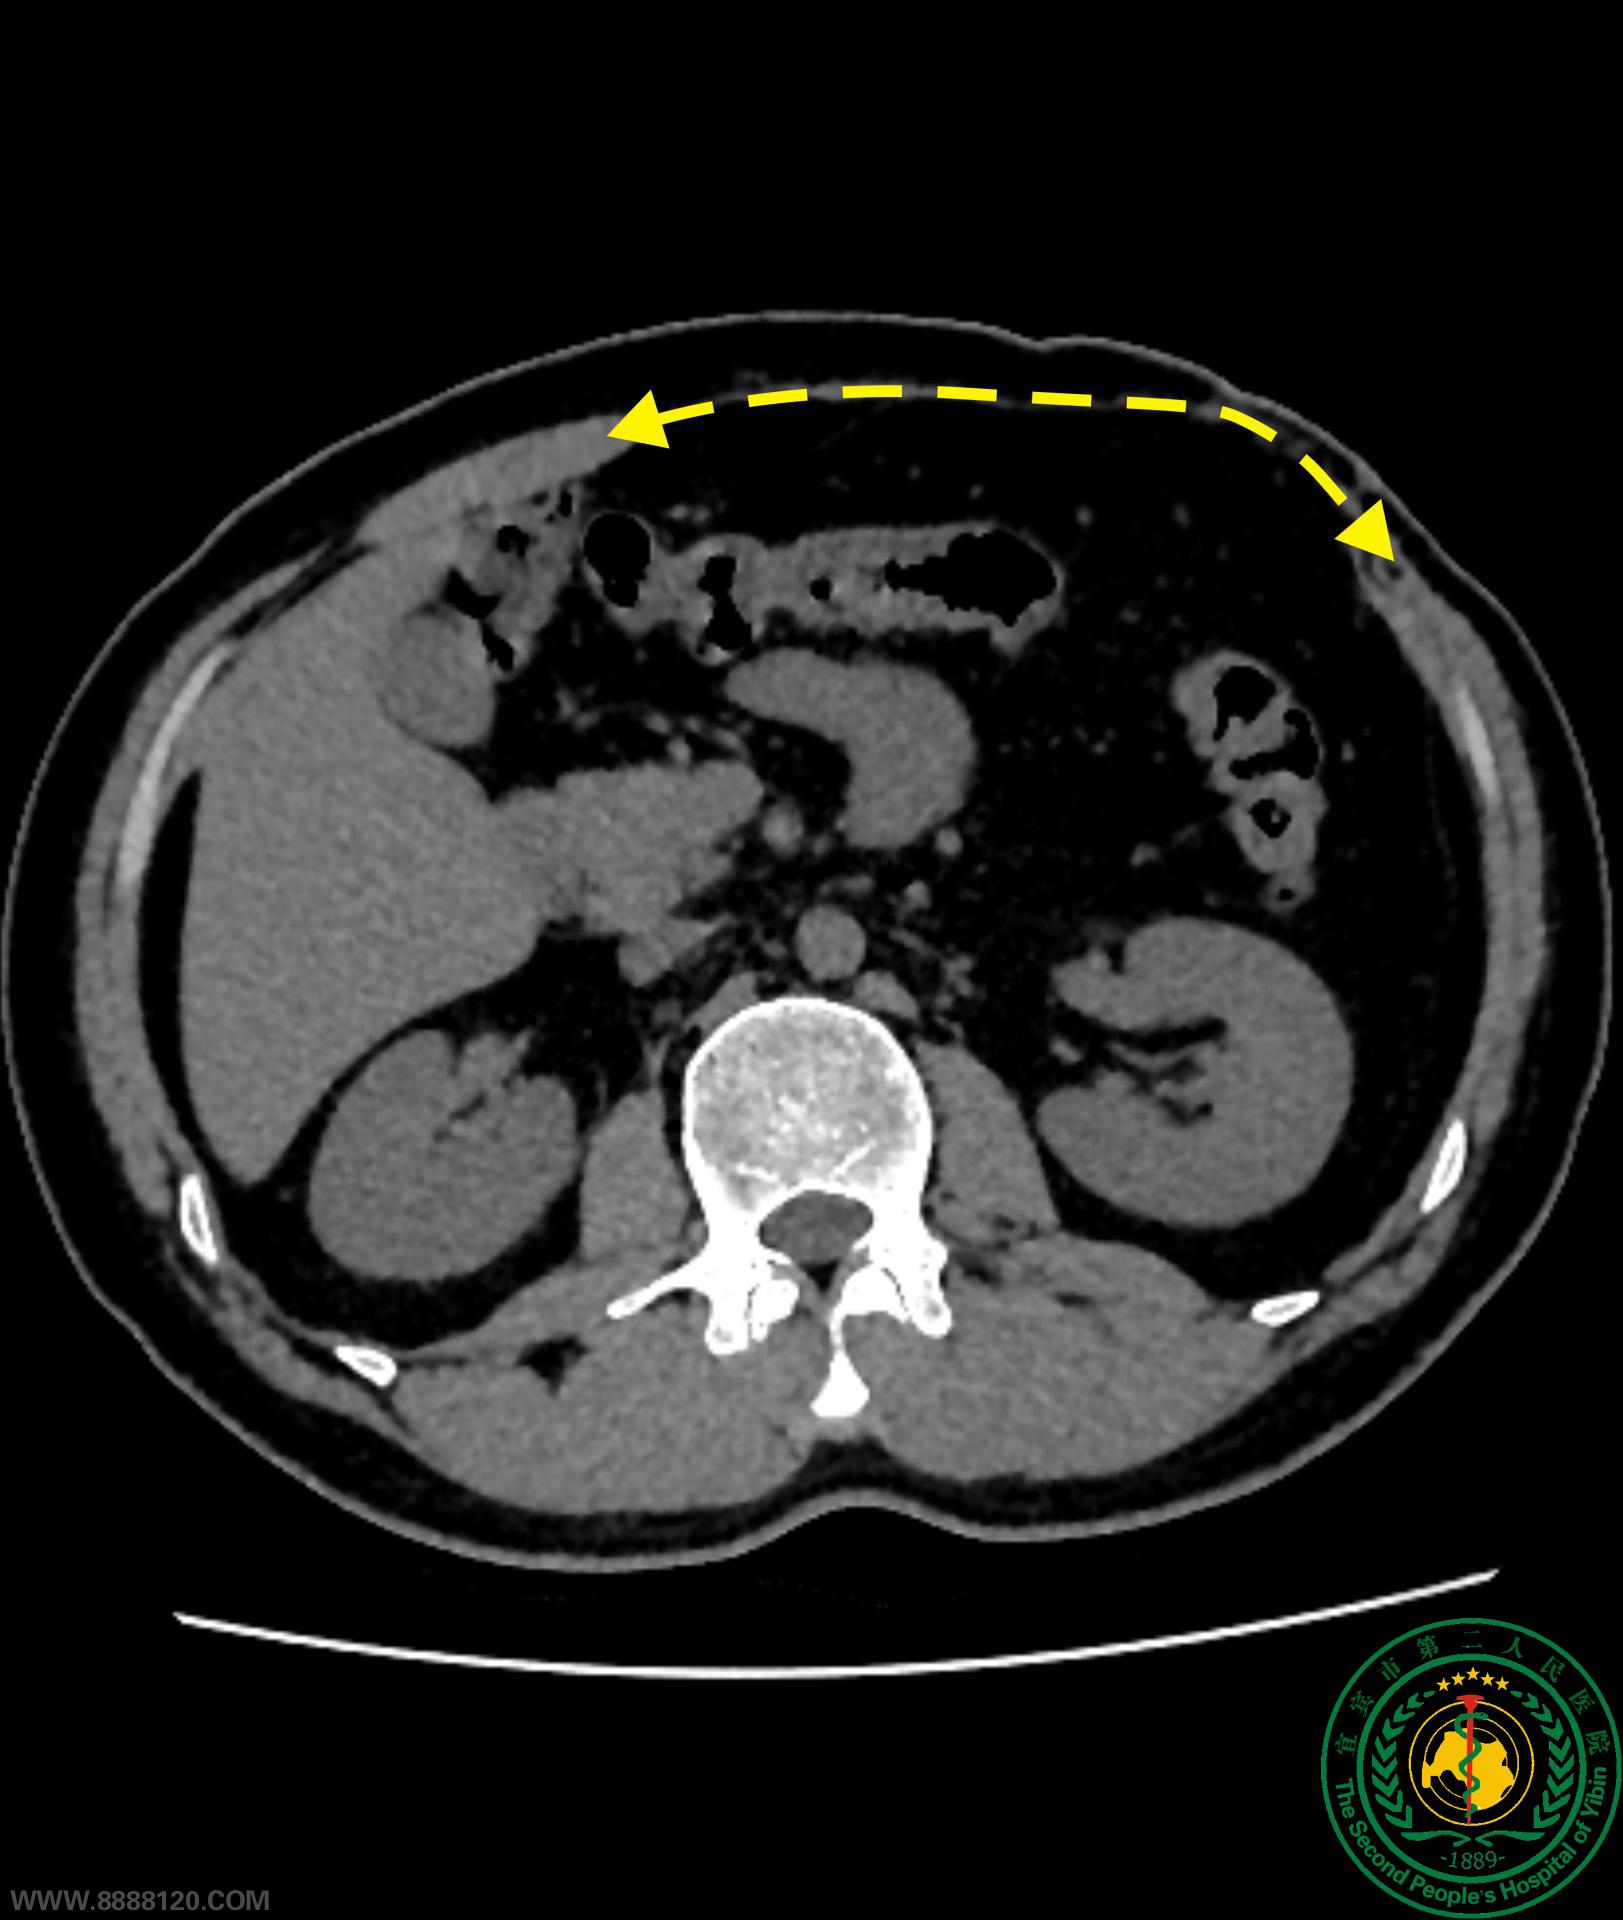

患者因“车祸伤”术后1年,反复突出性腹部包块来我院住院治疗。经CT发现患者腹壁属既往外伤手术后形成的沿肋缘巨大缺损、缺损范围约15×20cm。由于患者腹直肌萎缩明显,若采用组织分离重建技术(CST)重建腹壁,则可能导致患者腹壁功能损害,并发症增多。经过充分的评估及周密设计后,胃肠外科手术团队为其实施了完全腹腔镜腹壁缺损桥接、疝补片修补术。术后在快速康复流程指导下,术后当天正常进食、下床活动。